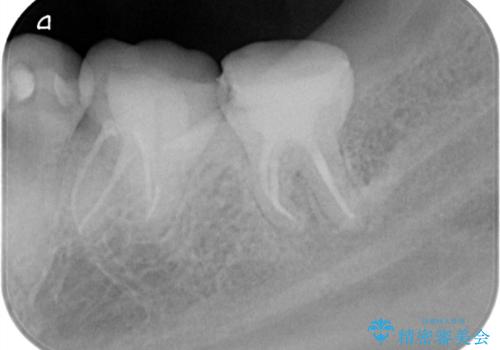

【根管治療】他院でインプラントの提案があった。奥歯が痛い。

- 左下の奥歯の治療の継続を主訴に来院されました。

1週間ほど前に、自発痛の既往があり他院で応急処置を行ってもらったとのことです。

そこでは、抜歯してインプラントの治療を提案されたとのことです。

レントゲンや口腔内所見にて以下のような説明ののち、患者様が保存を希望されたため、当院では根管治療~オールセラミッククラウンにて修復処置を行いました。痛みも消えて、経過良好です。

根尖部に透過像を認め、①何もしないと今後の経過として痛みが増悪することや、腫脹を伴うことがある。

病気の原因は細菌であるため、細菌数を減らすための処置として一般的に②根管治療という選択肢がある。再根管治療の場合は病気が治るのは7割ぐらいであり、それでも治らない場合は意図的再植術を行い9割近くまで成功率を高めることができる。ただし、今回のケースでは根尖が湾曲しているため意図的再植時の破折リスクが高いため適応は難しい。また、根尖の病変が治ったとしても、歯周病、カリエス、脱離や破折リスクがあり治療後抜歯になる可能性もある。治らない可能性や治療したとしても抜歯になる可能性があることを考慮し、③抜歯の選択肢をとる場合もある。